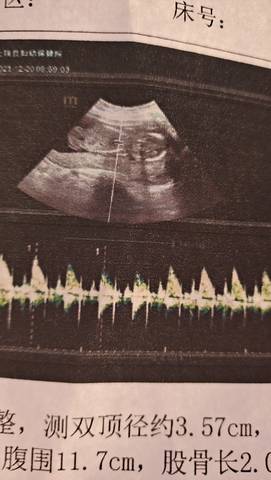

我这娃是横着的吗?保佑唐筛一定要过啊,躺等一个星期等结果。我好好躺着,你健康成长!

你这个胎盘低置的话,一定要卧床休息,尽量不太劳累的卡来回走动再去复查一下。